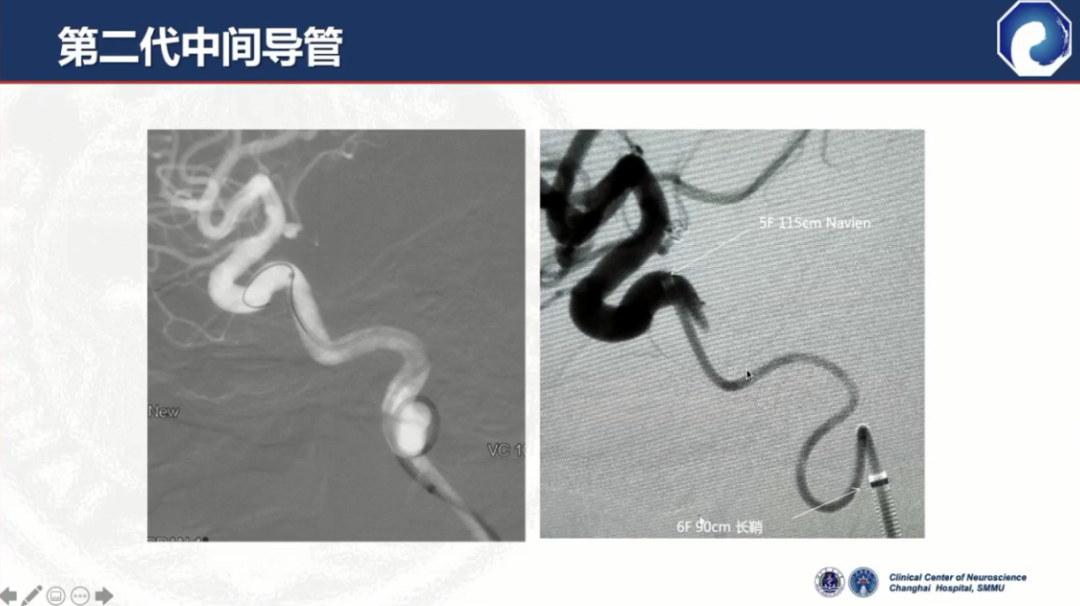

以Navien为代表的第二代中间导管诞生,通过性和到位能力有了显著提升

第二代中间导管仍存在血管内夹层等并发症,这也是所有导管都存在的问题。

此外,中间导管的支撑力比较差,近端需加长鞘或8F Guiding做支撑,需三轴系统